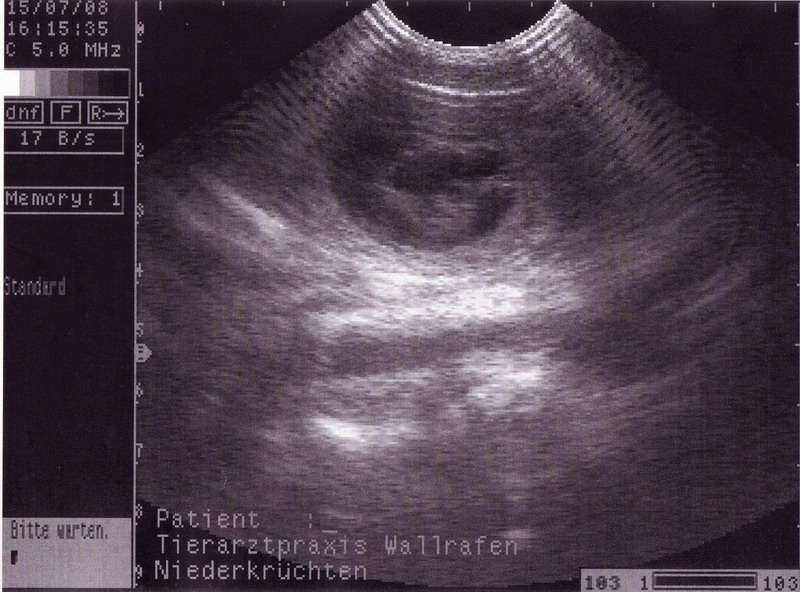

Es dauerte lange 30 Tage bis wir zum Ultraschall fahren konnten.

Wir waren "heute" beim Doc, und der zählte:

1...2....3....4....5... also mind. 4 bis 5 Welpen sind`s.. sagte er... wir sagen: Rest offen !